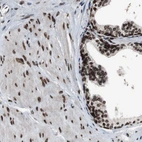

Immunohistochemical staining of human skin shows strong positivity in nuclear membrane in squamous epithelial cells.